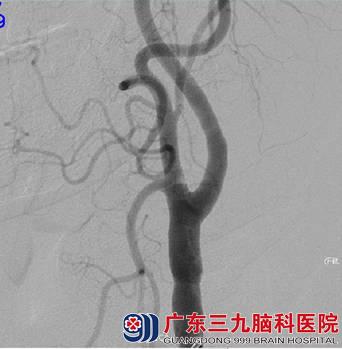

入院后医生查体,刁先生的语言不够流利,张口有限制,颅脑MRI提示:1.左侧额顶叶多发软化灶形成伴胶质增生、局限性脑萎缩,待排部分皮层层状坏死可能;2.双侧基底节-放射冠区、双侧丘脑、左侧半卵圆中心多发陈旧性腔梗灶;3D-ASL提示:左侧额顶枕叶呈低灌注;颈动脉彩超提示:双侧颈动脉粥样硬化(软斑);斑块造成左侧颈内动脉起始段重度狭窄。DSA提示:左侧颈内动脉起始部重度狭窄,狭窄率约80%。

图 3 术前DSA示:左侧颈内动脉起始部重度狭窄,狭窄率约80%;

图4 左侧颈内动脉起始部放大;